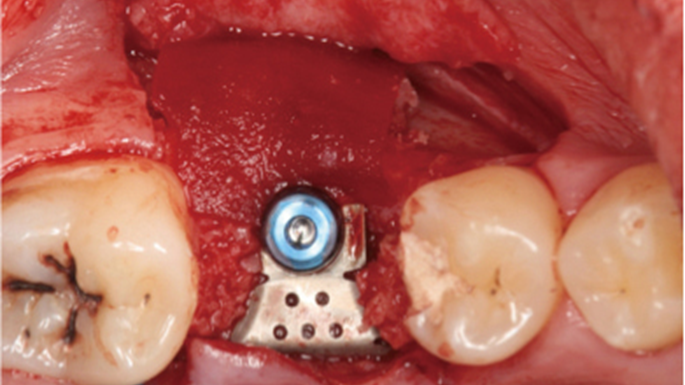

Clinical case: Ridge splitting technique using SmarThor + AnyRidge as expander

- Courtesy of Dr.Kwang-Bum Park, Korea -

Keywords

AnyRidge, ridge splitting, GBR, Dr. Kwang-Bum Park, mandibular posterior, SmartThor, Mega-Oss, thin ridge, bone regeneration

Products:

AnyRidge implant system. SmarThor, Mega-Oss